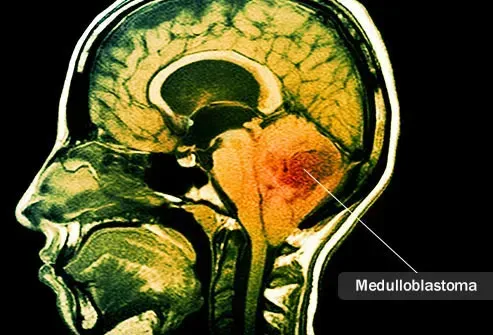

Les méningiomes gliomes et les glioblastomes sont les principaux types de tumeurs cérébrales primaires mais il y en a d'autres. Ils découlent de différentes zones du cerveau. Les adénomes sont des tumeurs qui se produisent dans l'hypophyse. Les chordomes sont des tumeurs cérébrales primaires qui se produisent dans la colonne vertébrale et le crâne. Les sarcomes sont des tumeurs cérébrales primaires qui découlent de la dure-mère (une couche de tissu Meninx qui tapisse la colonne vertébrale et le crâne) cartilage ou os. Les médulloblastomes sont des tumeurs cérébrales primaires qui découlent du cervelet qui fait partie du cerveau à l'arrière du crâne.